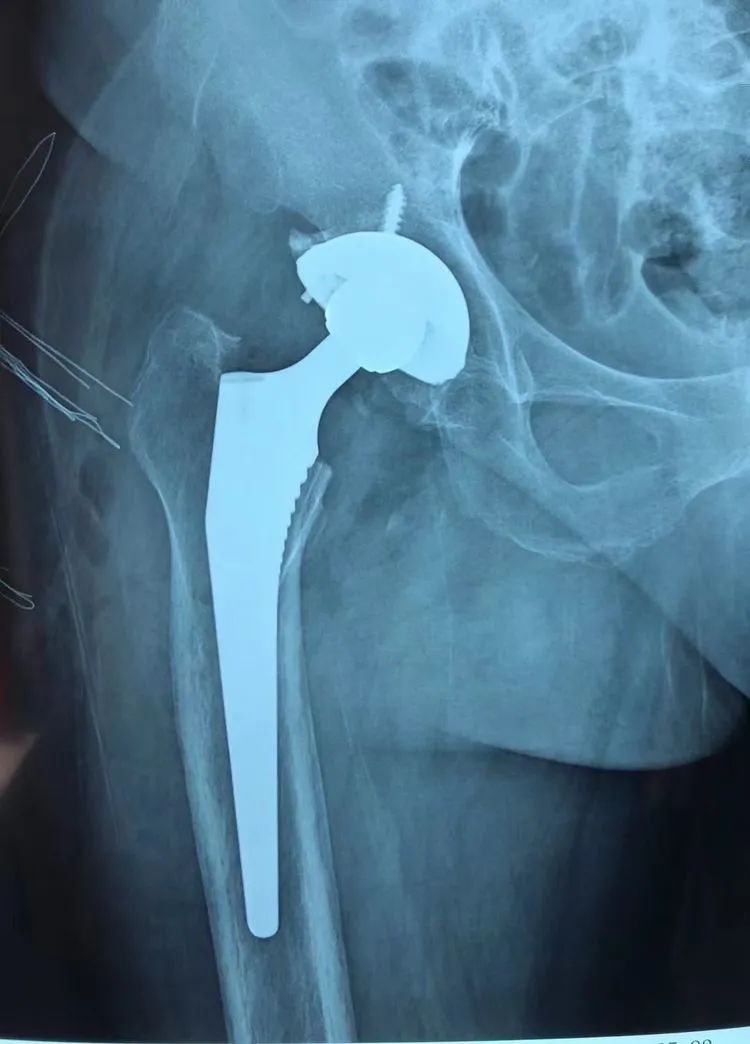

随后,在手术室团队的配合下,为其行腰硬联合麻醉下“右侧全髋关节置换术”,方成教授主刀,王怀波主任协同,熟练地切开、显露,切除、清理、安装......手术十分顺利。

家住寿县的马大娘,十五年前开始出现双侧髋关节疼痛,随着时间的推移,疼痛越来越厉害,腿不能屈,蹲也蹲不下。经人推荐,马大娘一家来到了淮南东方医院集团广济医院骨科就诊。完善检查后,明确诊断为“双侧先天性髋关节发育不良(DDH)、双侧股骨头无菌性坏死”,骨科王怀波主任邀请广济骨科首席专家方成教授共同开展术前讨论,迅速为其拟定“右侧全髋关节置换术”。